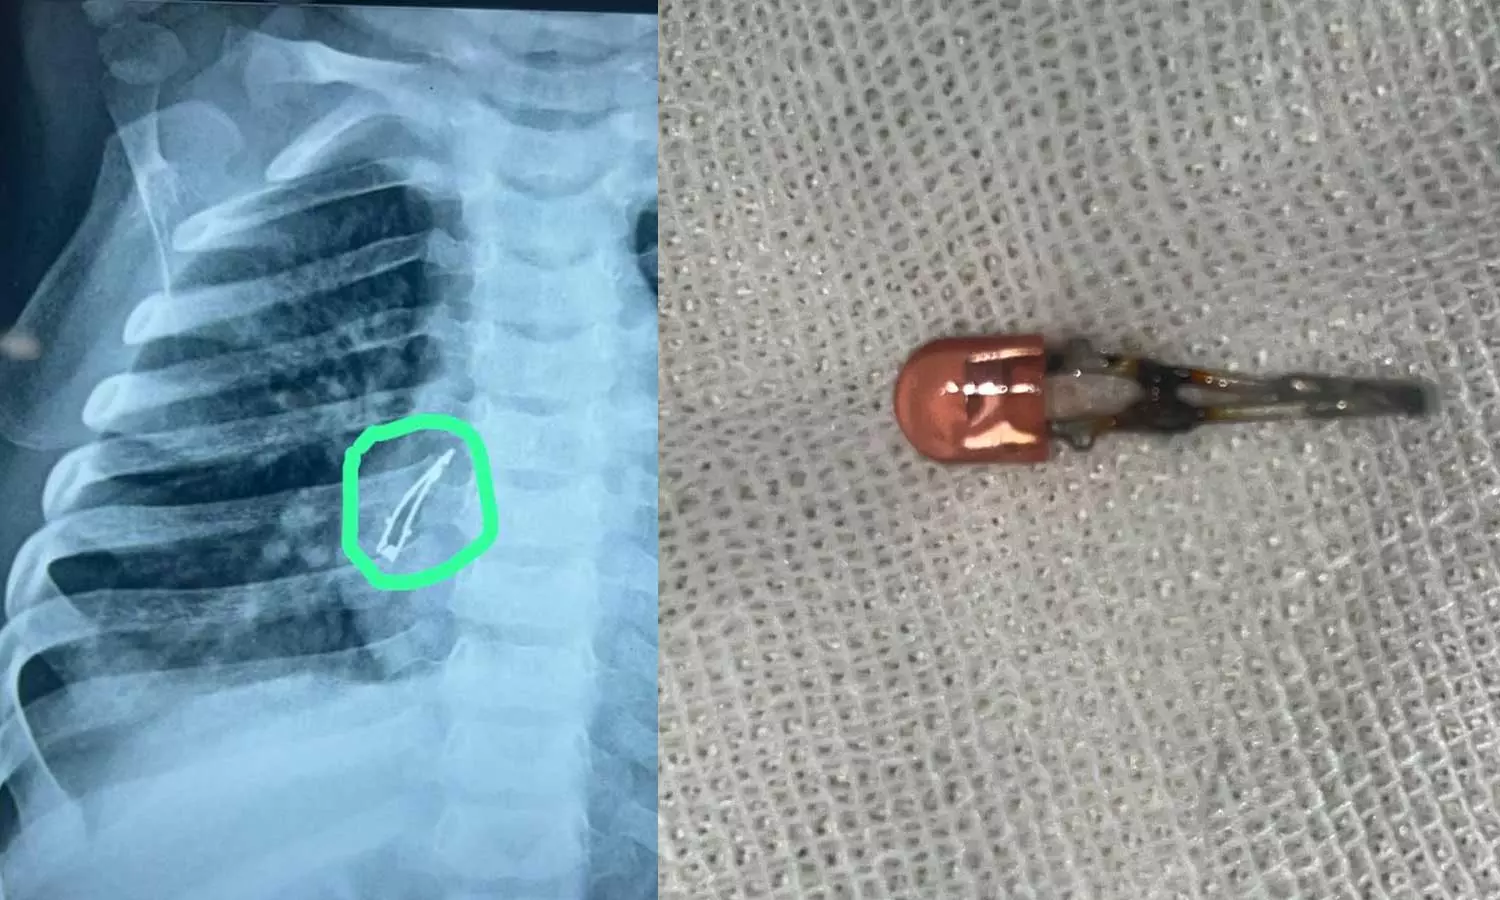

അഹമ്മദാബാദ്: ഒൻപത് മാസം പ്രായമുള്ള കുഞ്ഞ് അബദ്ധത്തിൽ വിഴുങ്ങിയ എൽഇഡി ബൾബ് ഓപ്പറേഷനിലൂടെ പുറത്തെടുത്തു. ഗുജറാത്തിലെ അഹമ്മദാബാദിലായിരുന്നു സംഭവം. രണ്ടാഴ്ചത്തോളം ചുമ മാറാത്തത് കൊണ്ടാണ് മുഹമ്മദ് എന്ന് പേരുള്ള കുട്ടിയെ അഹമ്മദാബാദ് സിവിൽ ആശുപത്രിയിൽ പ്രവേശിപ്പിച്ചത്.

ജുനഗഡിലെ ഒരു ശിശുരോഗ വിദഗ്ദ്ധനെയാണ് കുട്ടിയുടെ മാതാപിതാക്കൾ ആദ്യം സമീപിച്ചത്. അദ്ദേഹം തുടർ ചികിത്സയ്ക്കായി ആശുപത്രിയിലേക്ക് റഫർ ചെയ്യുകയായിരുന്നു. അവിടെ നടത്തിയ പരിശോധനയിലാണ് കുഞ്ഞിന്റെ ശ്വാസനാളത്തില് എല്ഇഡി ബള്ബ് കണ്ടെത്തിയത്. പിന്നീട് ബ്രോങ്കോസ്കോപ്പി നടത്തി കുഞ്ഞിന്റെ ശ്വാസനാളത്തിൽ നിന്ന് ബൾബ് നീക്കം ചെയ്തു.

കുട്ടി ആരോഗ്യവാനായിരിക്കുന്നു എന്നും ഉടൻ ആശുപത്രി വിടുമെന്നും അധികൃതർ അറിയിച്ചു. കുട്ടി കളിപ്പാട്ടം ഉപയോഗിച്ച് കളിക്കുമ്പോഴാണ് സംഭവം നടന്നതെന്ന് മാതാപിതാക്കൾ പറഞ്ഞു. എൽഇഡി ബൾബ് വേർപെട്ട് അബദ്ധത്തിൽ ഇത് വിഴുങ്ങുകയായിരുന്നു. ഇത് ചുമയ്ക്കും അസ്വസ്ഥതകൾക്കും കാരണമാവുകയായിരുന്നു.